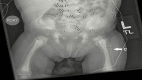

Osteopetrosis is a rare group of bone disorders characterized by defective osteoclast bone resorption causing high bone mineral density. A high bone mineral density in combination with defective skeletal mineralization results in a phenotype of osteopetrorickets. We present a rare presentation of infantile osteopetrorickets in an 8-week-old female who presented with failure to thrive, hypophosphatemia, anemia, and thrombocytopenia. A skeletal survey showed increased bone density with rachitic changes. She was found to have a homozygous T-cell immune regulator 1 (TCIRG1) pathogenic mutation consistent with osteopetrosis. This highlights the importance of a clinical suspicion of osteopetrosis with this symptom constellation.